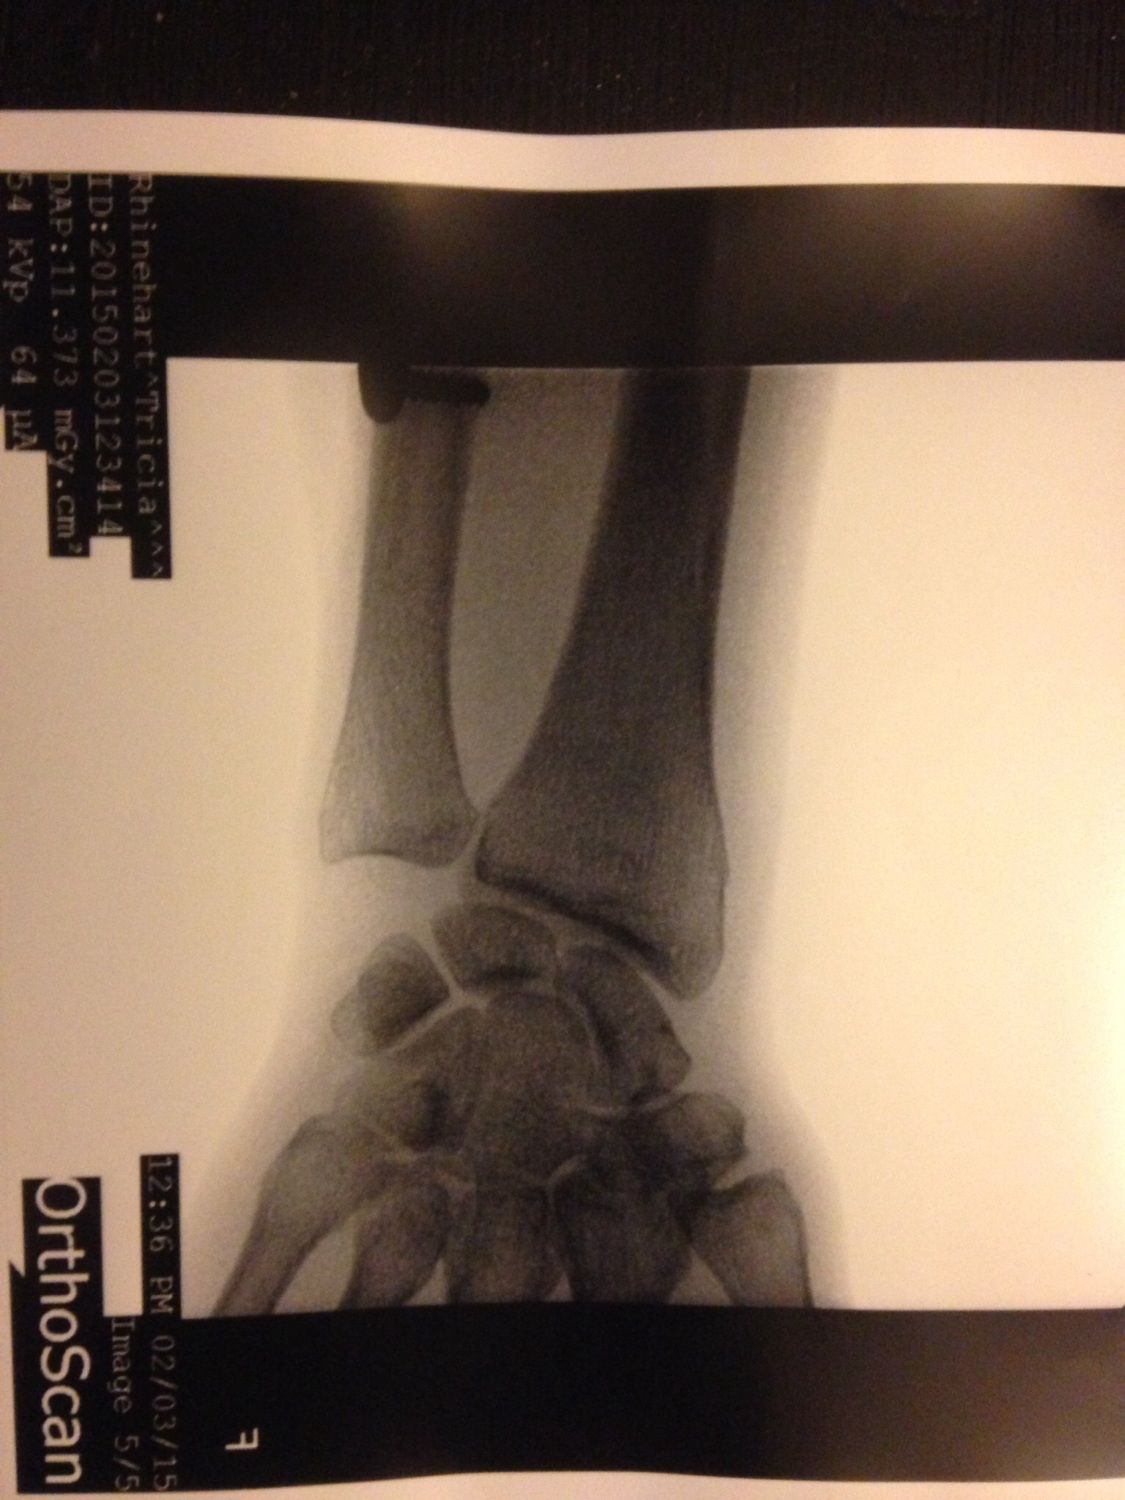

Here is a shot of my right arm with the plate and screws. With that and the hardware I my neck, I am one step closer to being bionic

Holy cow... that's crazy. How long does that stay in? I do hope you're not in to much pain.right!

Bionic woman! That would be cool, if it didn't not look like it hurt a lot! OUCH!!!right!